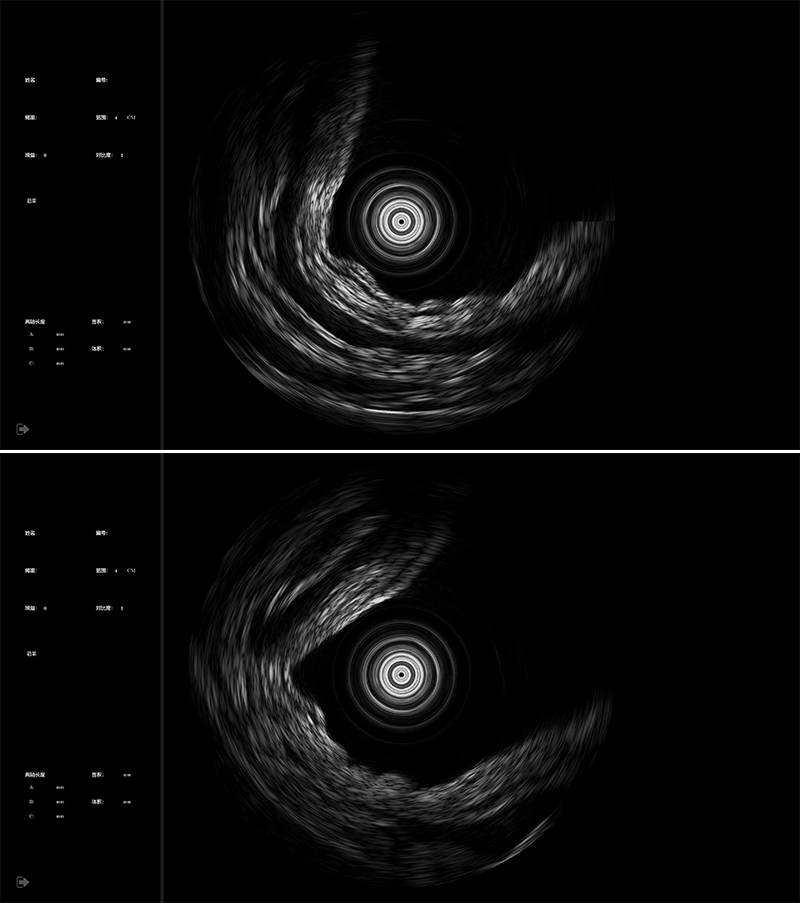

U1000 Endoscopy Ultrasound Scanner

360°mechanical loop scan probe

Multi-size microprobes meet diverse clinical needs

2D mechanical ring scan /3D spiral scan is optional

IPX7 waterproof rating, easy to clean and disinfect thoroughly